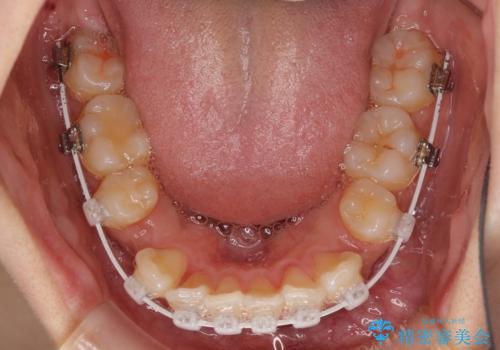

- 審美装置

- 2年5ヶ月

- 10-30回

下顎の正中を上顎に合わせる処置が難航し、期間が長引きました。